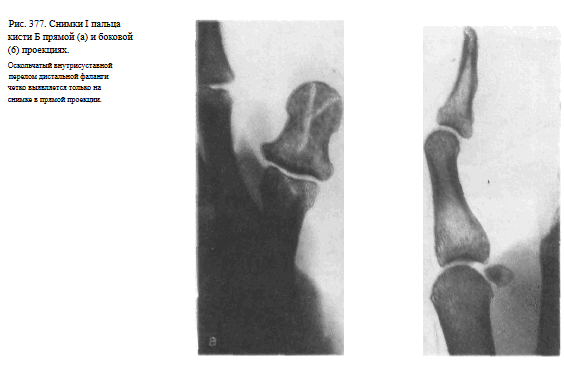

Видны наслаивающиеся друг на друга сесамовидные кости рядом с головкой I пястной кости (рис. 376). Снимки необходимо выполнять в двух взаимно перпендикулярных проекциях (рис. 377, а, б).

Снимок I пальцакисти в прямой тыльной проекции.

I палец прилежит к кассете тыльной поверхностью. Кисть и предплечье максимально ротированы кнутри. Для фиксации кисти в заданном положении больной удерживает ее здоровой рукой.

Используют кассету размером 13X1 8 см, перекрывая ее поперек листом просвинцованной резины.

Пучок рентгеновского излучения направляют отвесно на проекцию пястно-фалангового сустава (рис. 373).

На рентгенограмме видны фаланги и частично I пястная кость, их медиальные и латеральные поверхности, рентгеновские суставные щели пястно-фалангового и межфалангового суставов, бугристость дистальной фаланги (рис. 374).

Снимок I пальца в боковой проекции. I палец прилежит к кассете лучвым (наружным) краем.

Остальные пальцы слегка согнуты, опираются концами на перекрытую листом просвинцованно резины уже проэкспонированную половину кассеты.

Пучок рентгеновского излучения направлен на проекцию пястно-фалангового сустава (рис. 375).

На рентгенограмме выявляются тыльная и ладонная поверхности фаланг и частично I пястной кости.